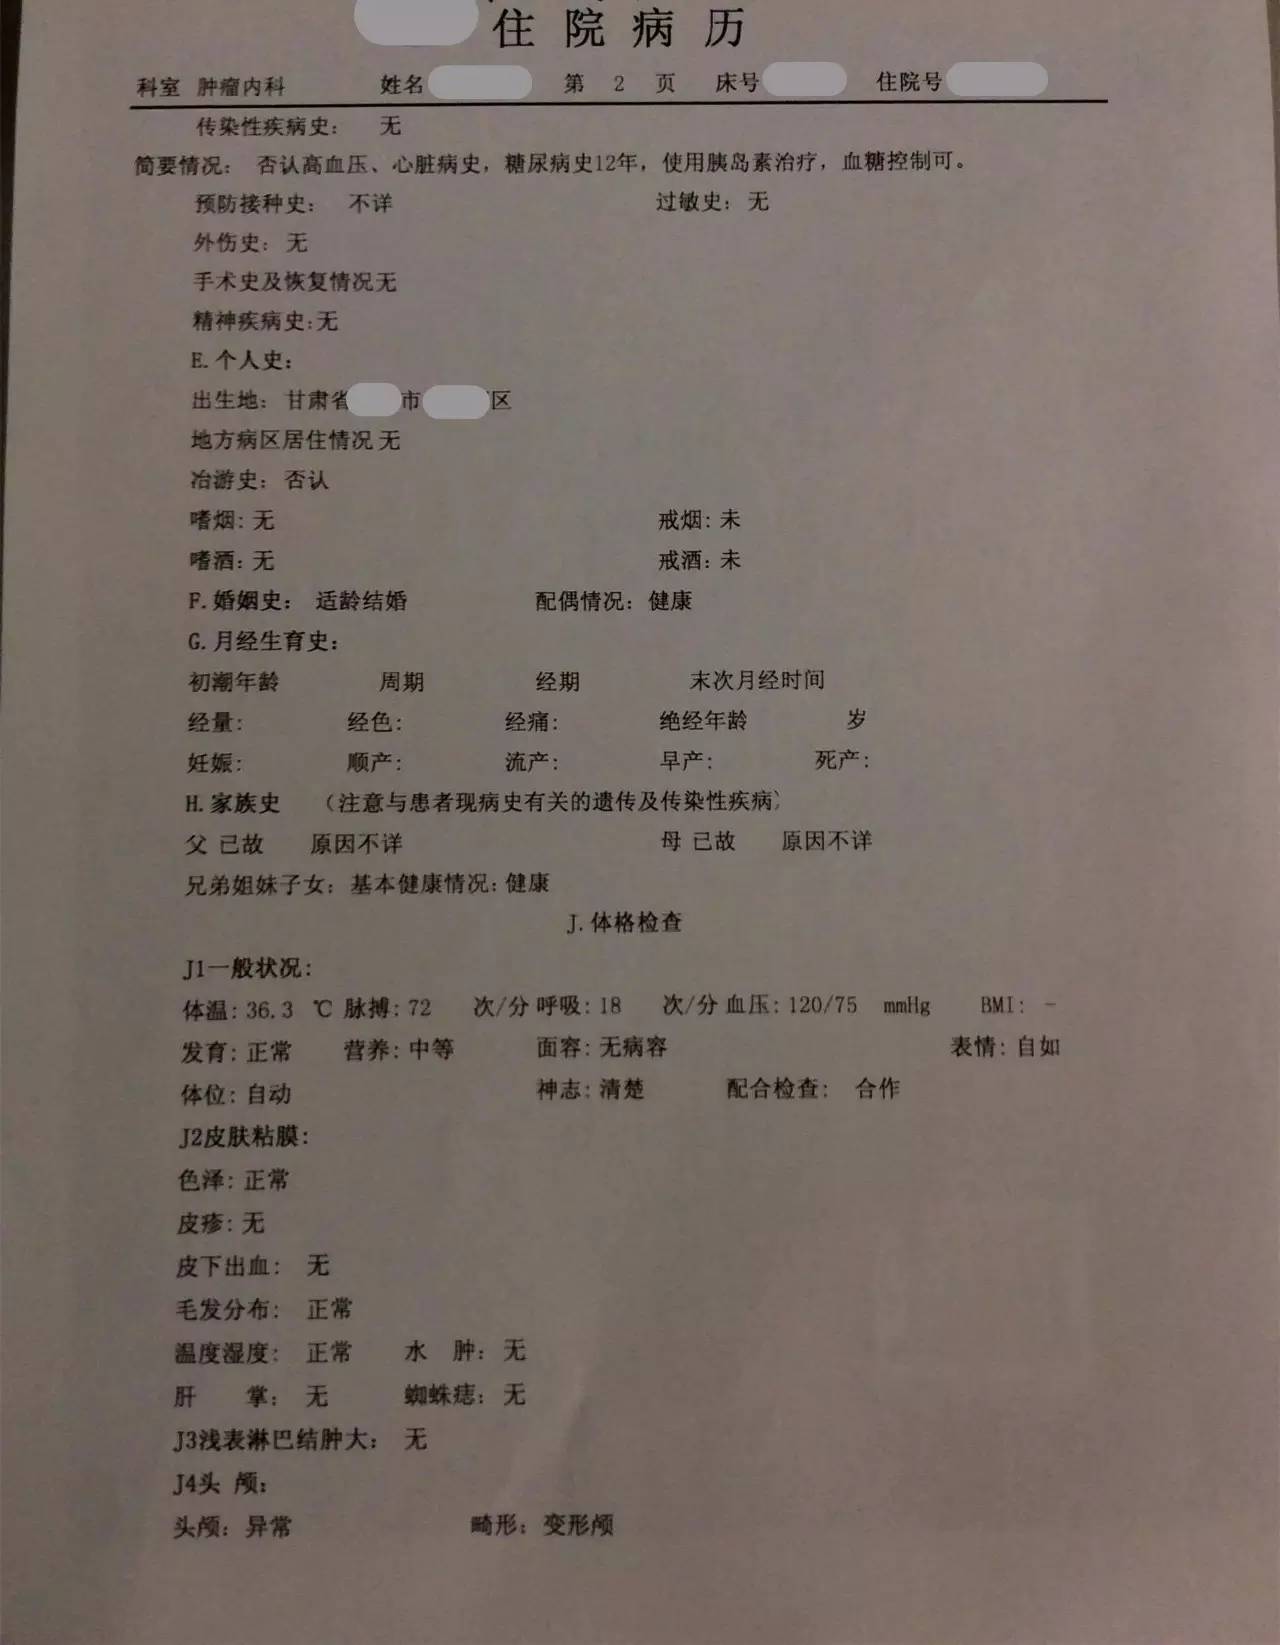

患者:男性,58岁,主因“左鼻腔高分化腺癌术后2年余”入院。

▼患者病情描述

复习病史,患者2013-7鼻内镜鼻腔肿物切除术,病理高分化腺癌,术后行同期放化疗,鼻腔局部照射65.72Gy/31f;2015-7出现前组脑神经损害症状体征,影像检查提示鼻腔及筛窦、额窦肿物,伴前颅底额叶异常强化及周围水肿,局部脑膜增厚、强化,颅底骨质不连续,考虑复发伴放射性改变;经鼻腔再次活检证实为复发;给予对症治疗症状加重,遂行PET/CT提示筛窦、双侧额叶、大脑镰、左侧眶周、海绵窦代谢增高;局部行射波刀治疗35Gy/6f,具体不详;疗后症状无明显缓解。首先双侧额叶改变MRI不能区别放射性脑坏死和肿瘤复发,可考虑进一步MRS、PWI、DWI成像提供更多的信息鉴别两者;倾向于肿瘤复发可能性大,原因如下:病变范围可能远远超出照射野;距放疗时间较短,文献报道一般放射性脑坏死中位发生时间约6年;颅底骨质破坏伴代谢增高,且与鼻腔、筛窦、左眶、海绵窦代谢一致。当然也不排除同时合并放射性损害,毕竟同时行化疗,可能较单纯放疗反应重。关于是否再行放疗改善症状,取决于前2次放疗的评价,看危及器官尤其是脑干、健侧视神经是否还能耐受;可使用卡马西平0.1、Tid,可能减轻神经痛症状;对症支持治疗方面适当应用激素、甘露醇等减轻脑水肿;也可考虑联合贝伐单抗;后续肿瘤治疗以化疗为主,请Z主任斟酌方案。